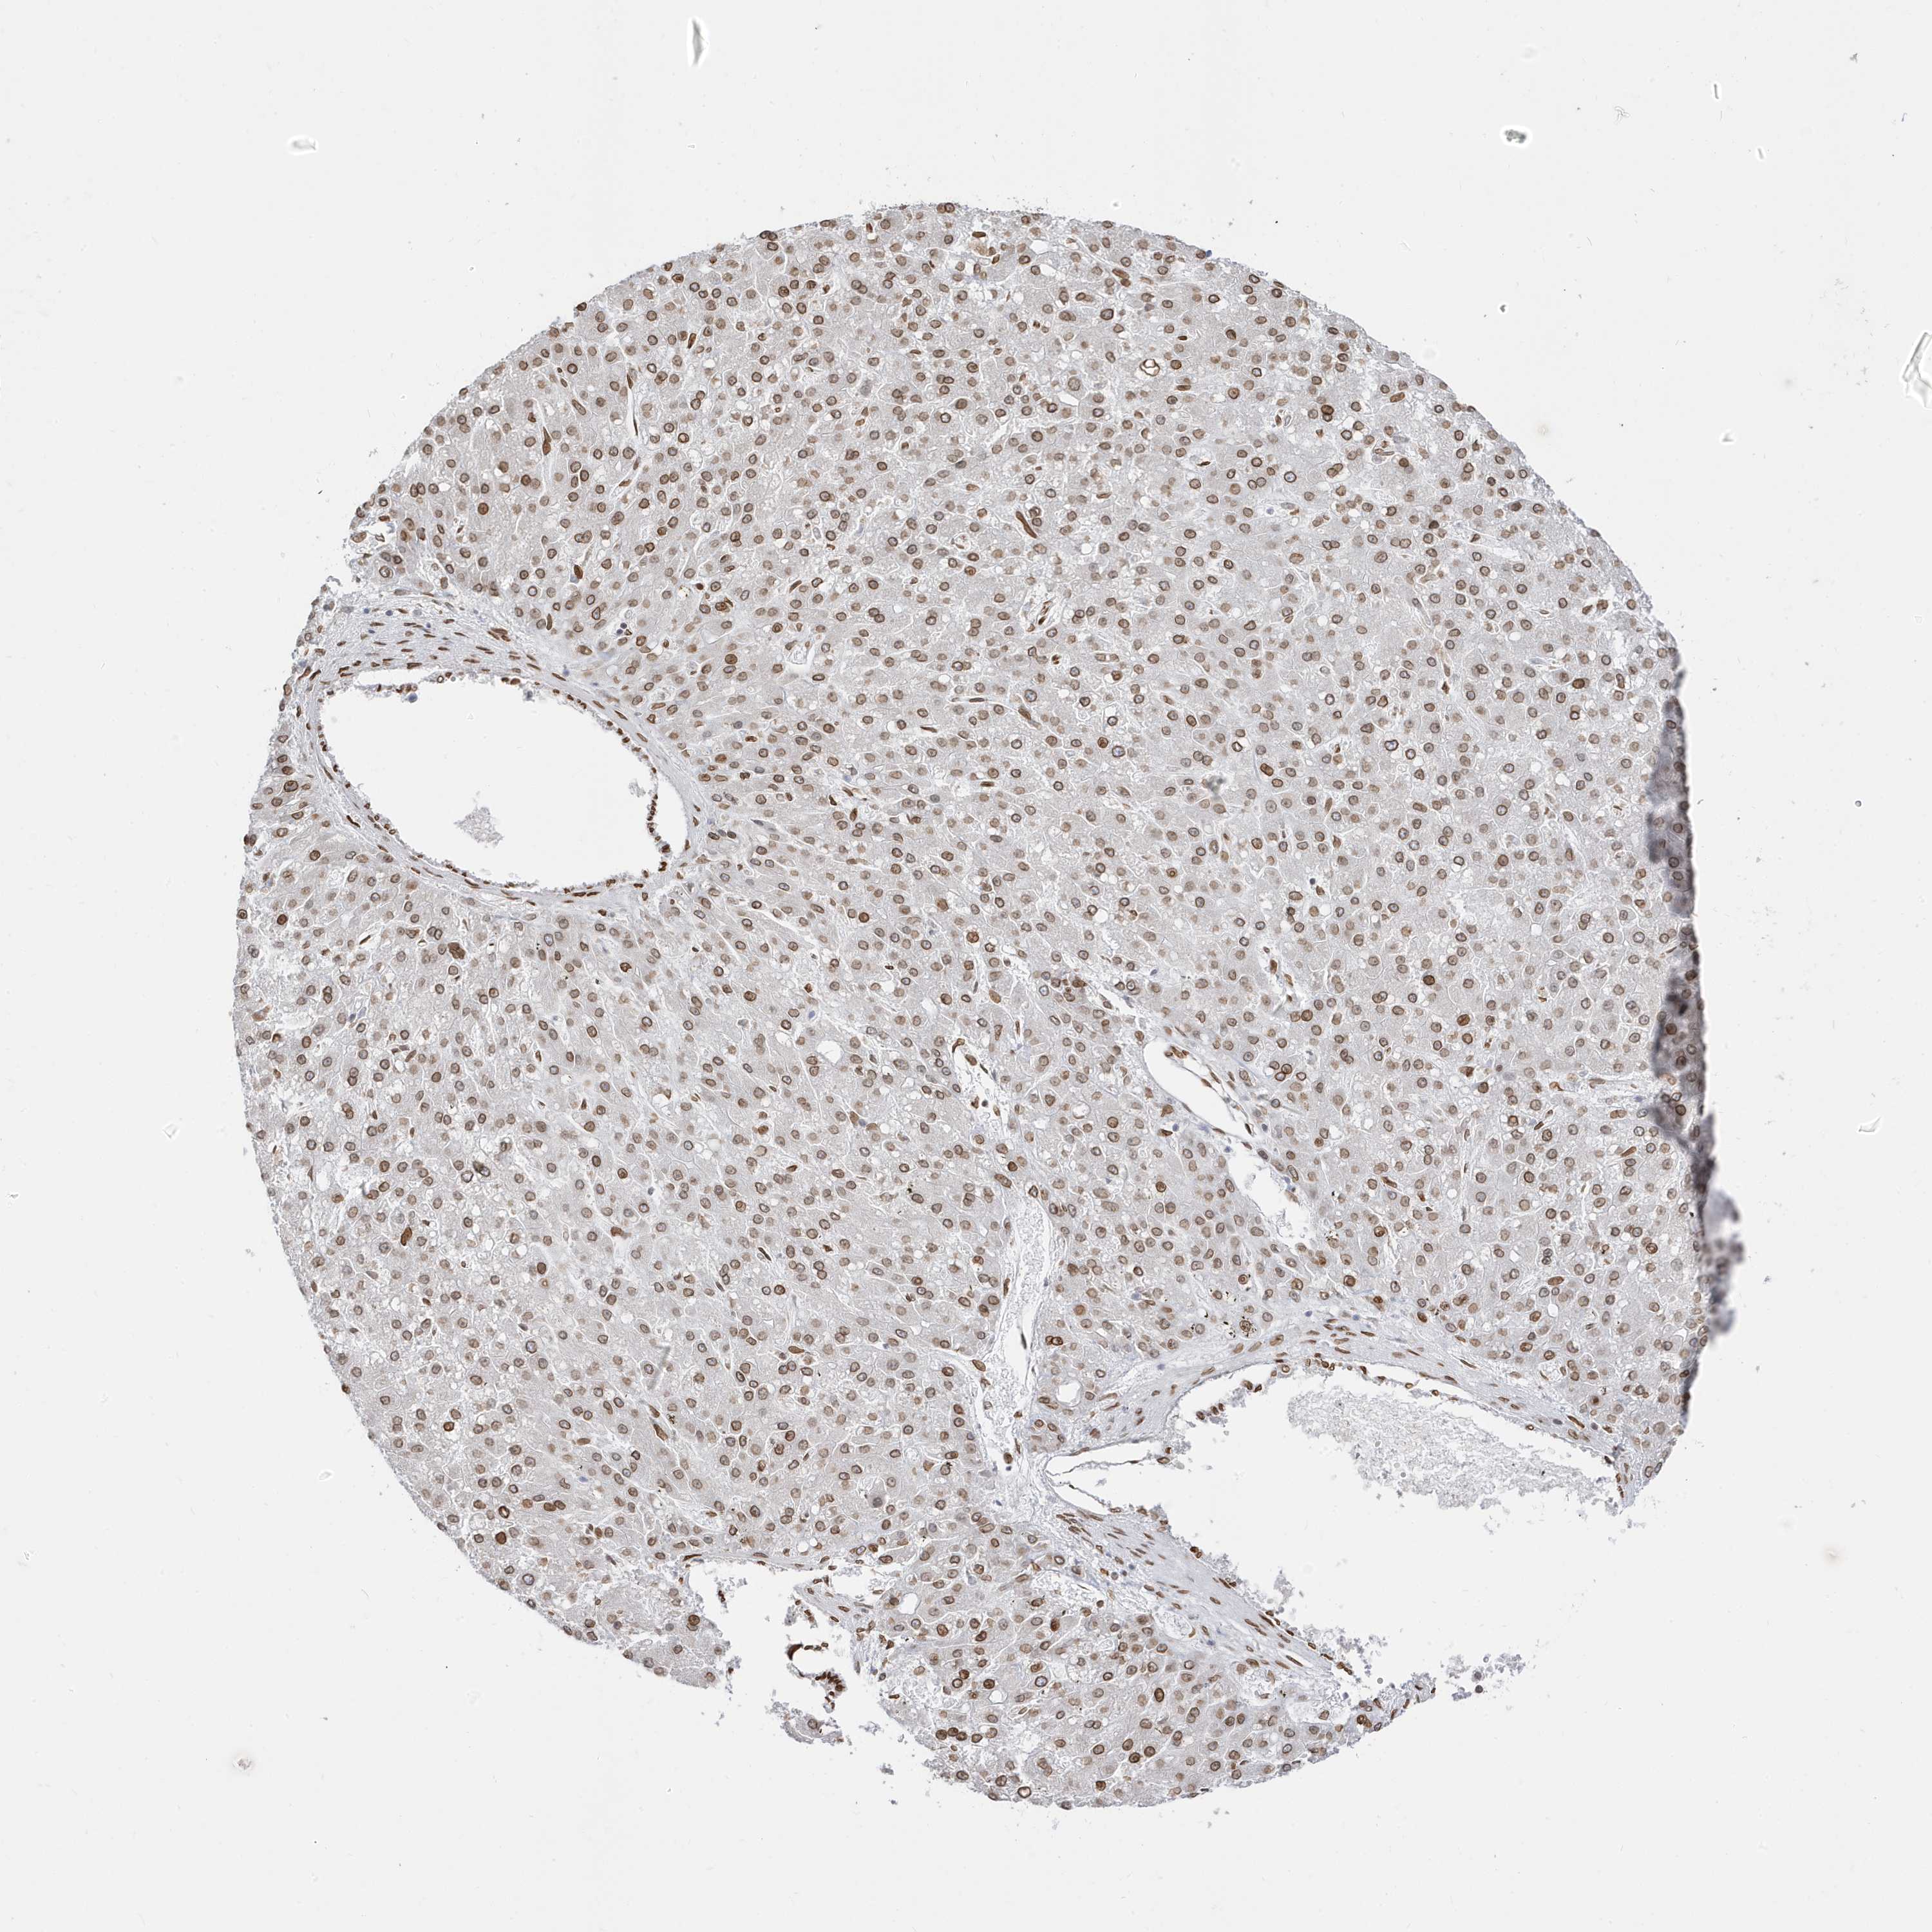

LIVER CANCER - Protein expressioni

A mouse-over function shows sample information and annotation data. Click on an image to view it in a full screen mode. Samples can be filtered based on level of antibody staining by selecting one or several of the following categories: high, medium, low and not detected. The assay and annotation is described here.

Note that samples used for immunohistochemistry by the Human Protein Atlas do not correspond to samples in the TCGA dataset.

Antibody stainingi

Antibody staining in the annotated cell types in the current human tissue is reported as not detected, low, medium, or high, based on conventional immunohistochemistry profiling in selected tissues. This score is based on the combination of the staining intensity and fraction of stained cells.

Each image is clickable and will lead to virtual microscopy that enables deeper exploration of all samples and also displays staining intensity scores, fraction scores and subcellular localization as well as patient and tissue information for each sample.

Antibody HPA029090

Staining

High

Medium

Low

Not detected

Intensity

Strong

Moderate

Weak

Negative

Quantity

>75%

75%-25%

<25%

None

Location

Nuclear

Cytoplasmic/membranous

Cytoplasmic/membranous,nuclear

Cholangiocarcinoma

Carcinoma, Hepatocellular, NOS